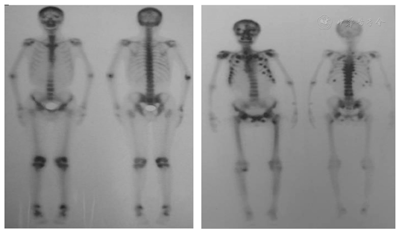

病例1,男,48岁,逐渐出现左踝关节、左下肢、左髋部疼痛2年后,来疼痛科就诊。疼痛以左侧髋关节处疼痛为主,为活动痛,呈持续性痛,VAS>7,有跛行,左髋叩痛(+),左下肢4字试验(+),骨盆X线片发现左髂骨、左股骨局部骨密度明显降低。骨盆CT未见异常,髋关节CT显示左股骨头及双侧股骨近端骨质密度不均匀,见图1。肿瘤全套检查显示甲胎蛋白13.32 ng/ml,余均正常。碱性磷酸酶317 U/L(正常值为15~112 U/L),尿酸125 μmol/L(男性正常值为210~430 μmol/L),磷0.46 mmol/L(正常值为0.80~1.60 mmol/L),尿素8.2 mmol/L(正常值为2.5~6.4 mmol/L),尿蛋白++++,尿隐血+++。骨髓瘤血液学检测(-),ECT显示:全身多发肋骨、关节骨代谢活跃,见图2。结合SPECT/CT及血磷明显降低,考虑低磷软骨症可能性大。追问既往史,患者有慢性乙型肝炎,服用阿德福韦酯10 mg,1次/d,5年,结合患者低尿酸、高碱性磷酸酶等异常,考虑为阿德福韦酯所致低血磷性骨软化症[1,2],并引起下腰痛。遂嘱患者停用阿德福韦酯,用口服拉米夫定(lamivu-dine)代替,并口服骨化三醇(calcitriol)和碳酸钙D3,促进钙,磷的吸收。疼痛逐渐好转,3个月后,疼痛完全消失,下肢活动恢复正常,血磷,尿酸等各项指标均在正常范围内,见表1。